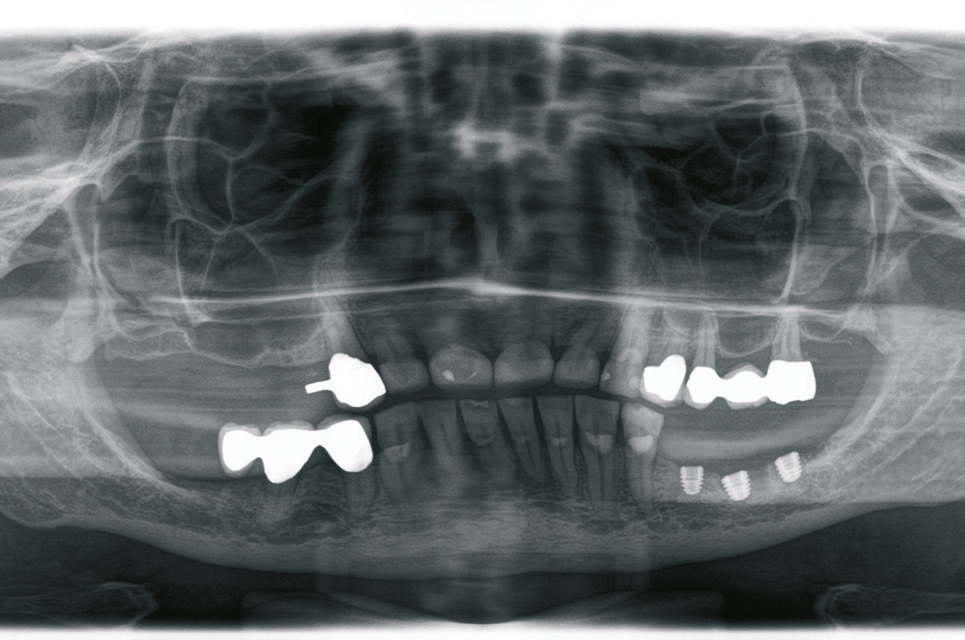

Beim Fehlen von mehreren Zähnen können unterschiedliche Planungs- und Versorgungskonzepte zur Anwendung kommen. Zur Kompensation der geringeren Verankerungsfläche von kurzen Implantaten im Knochen wird neben der Zahn-für-Zahn-Versorgung eine Verblockung von multiplen Implantaten empfohlen [6]. Die Empfehlungen sind aber im Kontext der jeweiligen Implantat- Aufbau-Verbindung, die bei der Versorgung von kurzen Implantaten zur Anwendung gekommen ist, zu berücksichtigen. Aus dem Anwendungsbereich der Implantate mit einer externen Implantataufbauverbindung wird eine Verblockung angeraten, um eine ausreichende Stabilität besonders bei einer hohen Aufbauhöhe des Zahnersatzes sicher zu stellen [6]. Die Erfahrung bei der Anwendung von Implantaten mit einer konischen Implantataufbauverbindung hat gezeigt, dass sich multiple Einzelkronen langzeitstabil eingliedern lassen [2] (Abb. 9-14). Besonders in Hinblick auf das periimplantäre Knochenniveau wird davon ausgegangen, dass sich bei der Einzelversorgung keine Spannungen auf Grund einer unzureichenden zahntechnischen Herstellungsgenauigkeit ergeben können.

Zeigt sich im Rahmen der Planung, dass das vertikale Knochenangebot nur in einem Bereich des zahnlosen Kieferkammabschnittes vorliegt, können kurze Implantate auch mit längeren Implantaten kombiniert werden. Dann kann anstelle der multiplen Einzelversorgung auch eine Brückenversorgung angegangen werden (Abb. 15-18). Bei der Verblockung von Implantaten mit einer konischen Implantataufbauverbindung muss auf eine genaue Übertragung der Implantatanschlussgeometrie geachtet werden, da es durch die Toleranzen bei der Herstellung des Konus zu einem vertikalen Versatz kommen kann. Im Vergleich zu Implantaten mit einer zylindrischen, parallelen Verbindung fehlt hier der Anschlag, der eine genaue Übertragung der vertikalen Position sicherstellt. Um diesen vertikalen Fehler zu vermeiden empfiehlt es sich auf Abutmentniveau abzuformen. In diesem Fall kann das Abutment auch in-situ verbleiben, so dass das periimplantäre Weichgewebe nicht mehrfach traumatisiert wird.